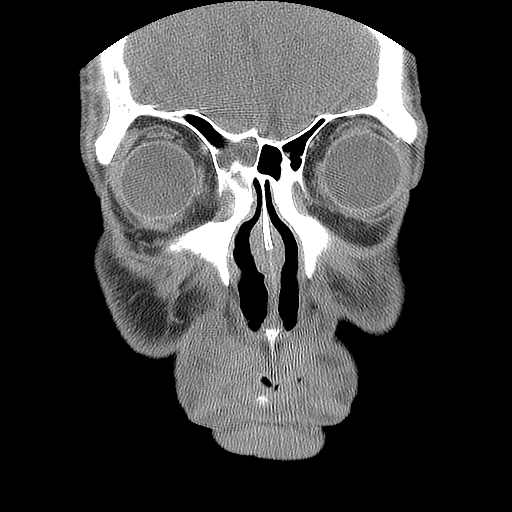

男,38岁,鼻塞、头痛2个月,要求鼻窦ct检查。

右侧上颌窦、蝶窦、筛窦、额窦及左侧上颌窦慢性炎症。

右侧鼻中隔左偏,右侧上颌窦、筛窦、额窦慢性炎性病变。右侧上颌窦开口粘膜增厚。

1)副鼻窦炎。2)右侧中鼻道及总鼻道粘膜息肉样变。3)双侧中下鼻甲肥大。4)鼻中隔轻度左突偏曲。